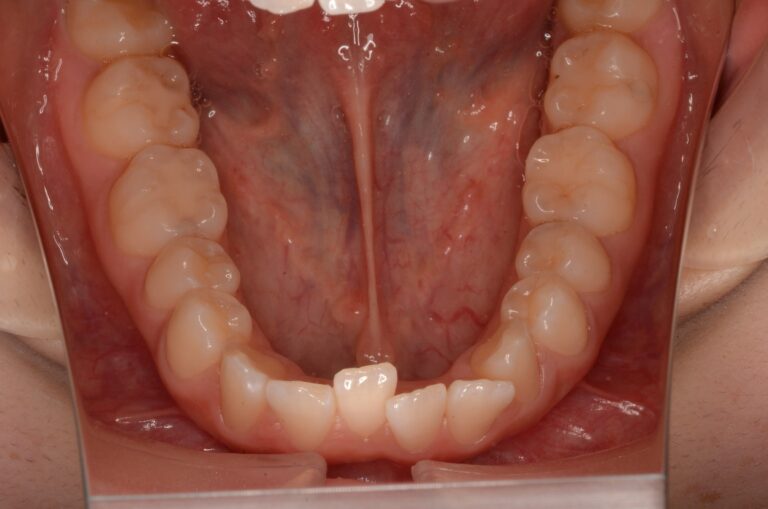

症例2:八重歯が気になる

| 患者様データ | 20代 女性 |

| 来院主訴 | 八重歯が気になる。 |

| 治療内容 | 八重歯を治すために上の親知らずを抜歯し、インビザラインにてマウスピース矯正を開始しました。かみ合わせを整えるためにゴムかけを行いました。 |

| 概算治療費 | 約85万円 |

| 治療期間 | 1年3ヶ月 |

| 通院回数 | 8回 |